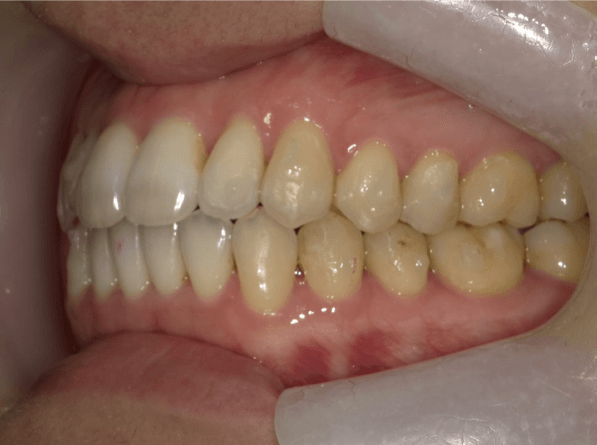

叢生(狭窄歯列弓)

BEFORE

AFTER

担当医コメント

下顎の歯が内側に倒れ狭窄歯列弓になっている。下顎を拡大することで下顎の歯列を整える計画をし、インビザラインで治療をする事にした。

治療の概要

年齢/性別

39歳 男性

主訴

下の歯の並びがガタガタなので、歯磨きがしにくいので治したいでした。

リスク

下顎の叢生改善時に歯肉退縮が起こる可能性がある

費用

82万円(矯正費用)

期間

8ヶ月

術前

術後